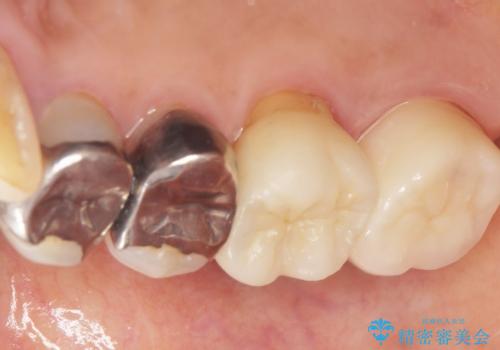

- 奥歯に歯ブラシをあてると痛みがあることを主訴に来院された患者様です。

精査したところ、右上奥の銀歯(右上7)は適合不良により二次う蝕になっていました。

銀歯を外してう蝕を丁寧に除去したのち、オールセラミッククラウンによる補綴治療を行いました。